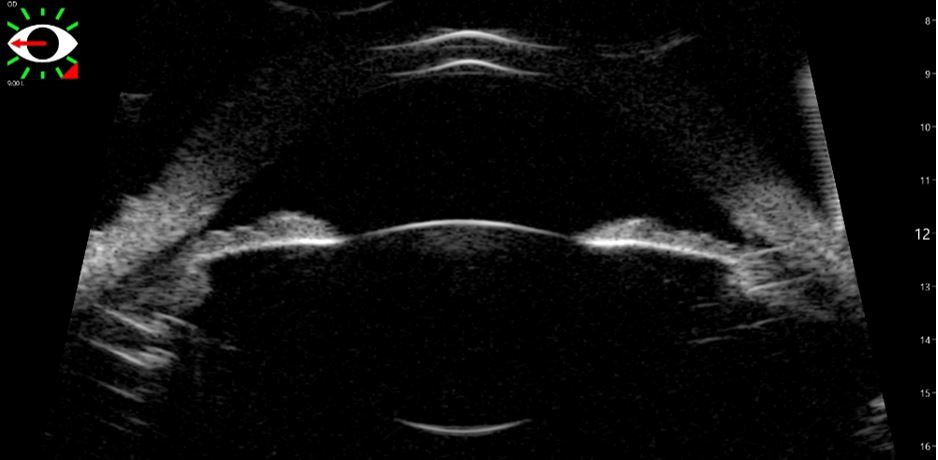

The ArcScan Insight® 100 is an intelligent anterior segment imaging system that uses very high frequency ultrasound technology. The ArcScan Insight® 100 device and software create a powerful platform that enables users to easily obtain stunning high resolution images in micron precision of the entire anterior segment, including areas that can not be imaged with optical technologies.

Precision imaging behind the iris for better ICL/IOL sizing.